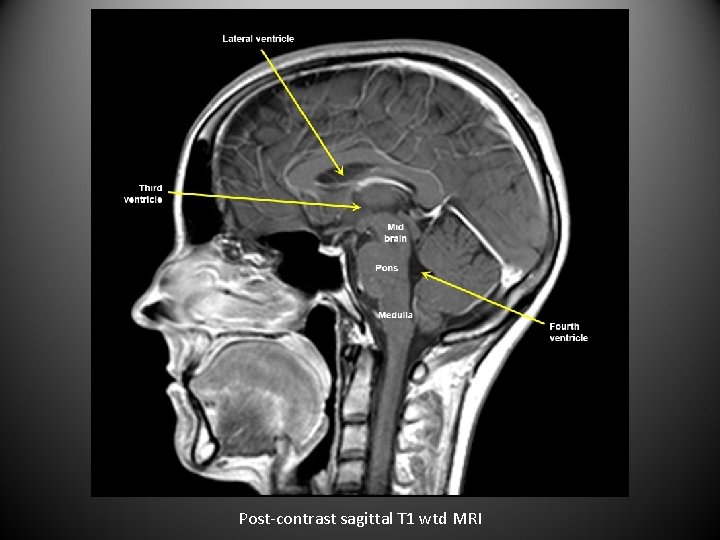

Post-contrast sagittal T 1 wtd MRI